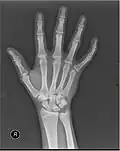

Left hand shown with thumb on left.

The metacarpals form a transverse arch to which the rigid row of distal carpal bones are fixed. The peripheral metacarpals (those of the thumb and little finger) form the sides of the cup of the palmar gutter and as they are brought together they deepen this concavity. The index metacarpal is the most firmly fixed, while the thumb metacarpal articulates with the trapezium and acts independently from the others. The middle metacarpals are tightly united to the carpus by intrinsic interlocking bone elements at their bases. The ring metacarpal is somewhat more mobile while the fifth metacarpal is semi-independent.[1]

Each metacarpal bone consists of a body or shaft, and two extremities; the head at the distal or digital end (near the fingers), and the base at the proximal or carpal end (close to the wrist).